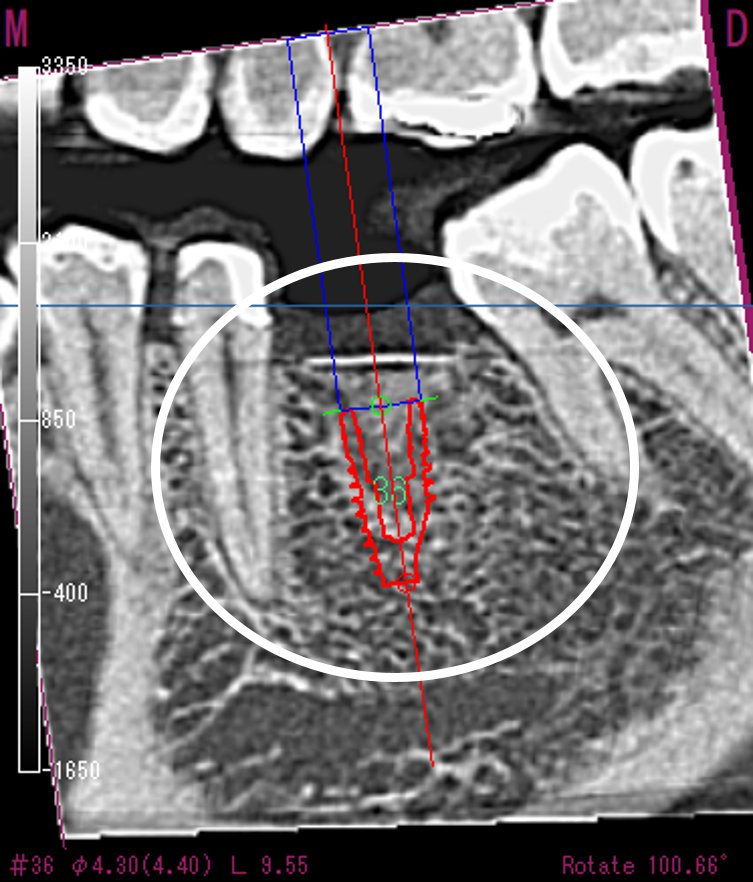

CT画像解析後、インプラントのシミュレーションを行い、理想的な位置に埋入出来ることを確認。この位置に、正確に入れていくための、サージカルガイドをコンピューターで製作しました。